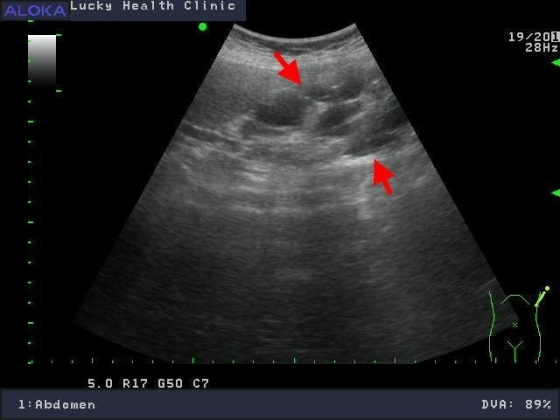

多囊腎

醫學影像..腹部超音波 :腎臟